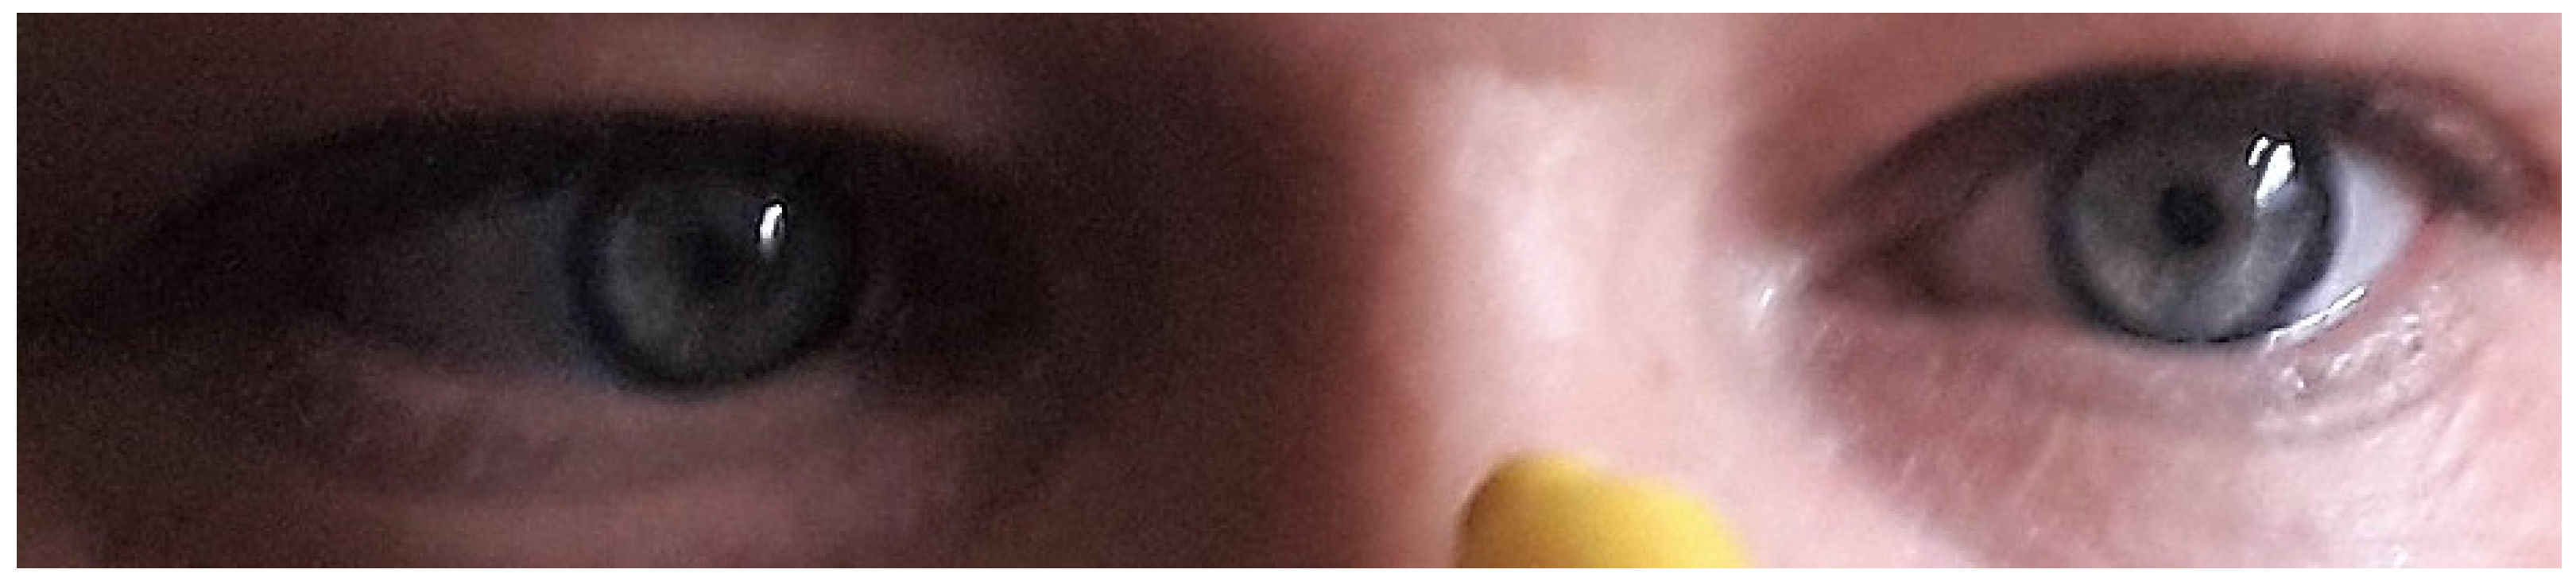

The acuity of vision of both eyes was not disturbed once the episodes of transient vision loss had subsided (Snellen chart 1.0; no retractive disorders: the right eye +0.25/−0.5/93, the left eye +2.0/−0.5/45). Concomitant symptoms included loss of the nasolabial fold as well as increased deep tendon reflexes of the upper-left limb. The orthoptic examination revealed convergence insufficiency (Figure 1) and left-eye exophoria, confirmed with the Maddox test; however, neither the assessment of binocular vision nor the examination of the mobility of the extraocular muscles in the Hess screening revealed any dysfunction.

Figure 1.

Convergence insufficiency of the left eye. The patient has agreed to the publication of this photo—proper consent was obtained.